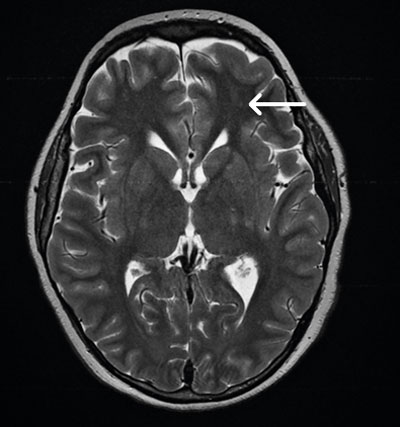

Vid ankomst till IVA var han svår att syresätta (FiO2 [inandad syrgasfraktion] på 80 procent) men cirkulatoriskt stabil. Patientens ordinarie läkare var bakjour det aktuella dygnet. Fettembolisyndrom misstänktes med tanke på den kliniska bilden. Lungröntgen tolkades initialt som påvisande aspiration. Datortomografi (DT) av lungartärer på misstanke om lungemboli (Figur 1) samt en DT av skalle på misstanke om fettemboli gjordes. Datortomografin av lungartärer bedömdes som aspirationspneumoni, och den sämre kontrastfyllnad som ses i enstaka subsegmentella artärer i både höger och vänster lunga tolkades i första hand som flödesbetingad och antibiotika sattes in. DT av knän bilateralt visade odislokerade typ 2-frakturer enligt Salter–Harris frakturklassifikation (Figur 2 A och B), som gipsbehandlades.

Figur 2. Datortomografi av knän påvisande bilaterala, odislokerade typ 2-frakturer enligt Salter–Harris i distala femur (vita pilar). A höger sida och B vänster sida.